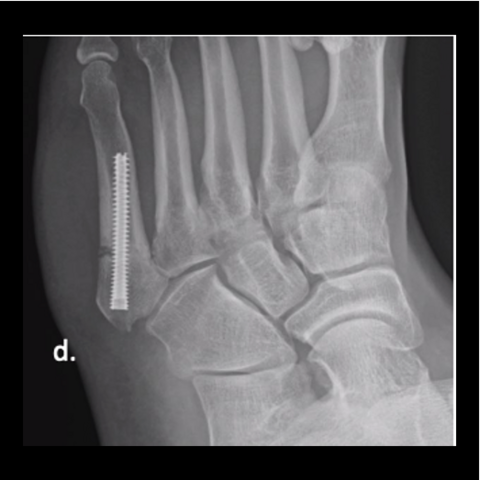

Figure 3d

Figure 3d. Here is the 28-year-old’s foot at 6 weeks.